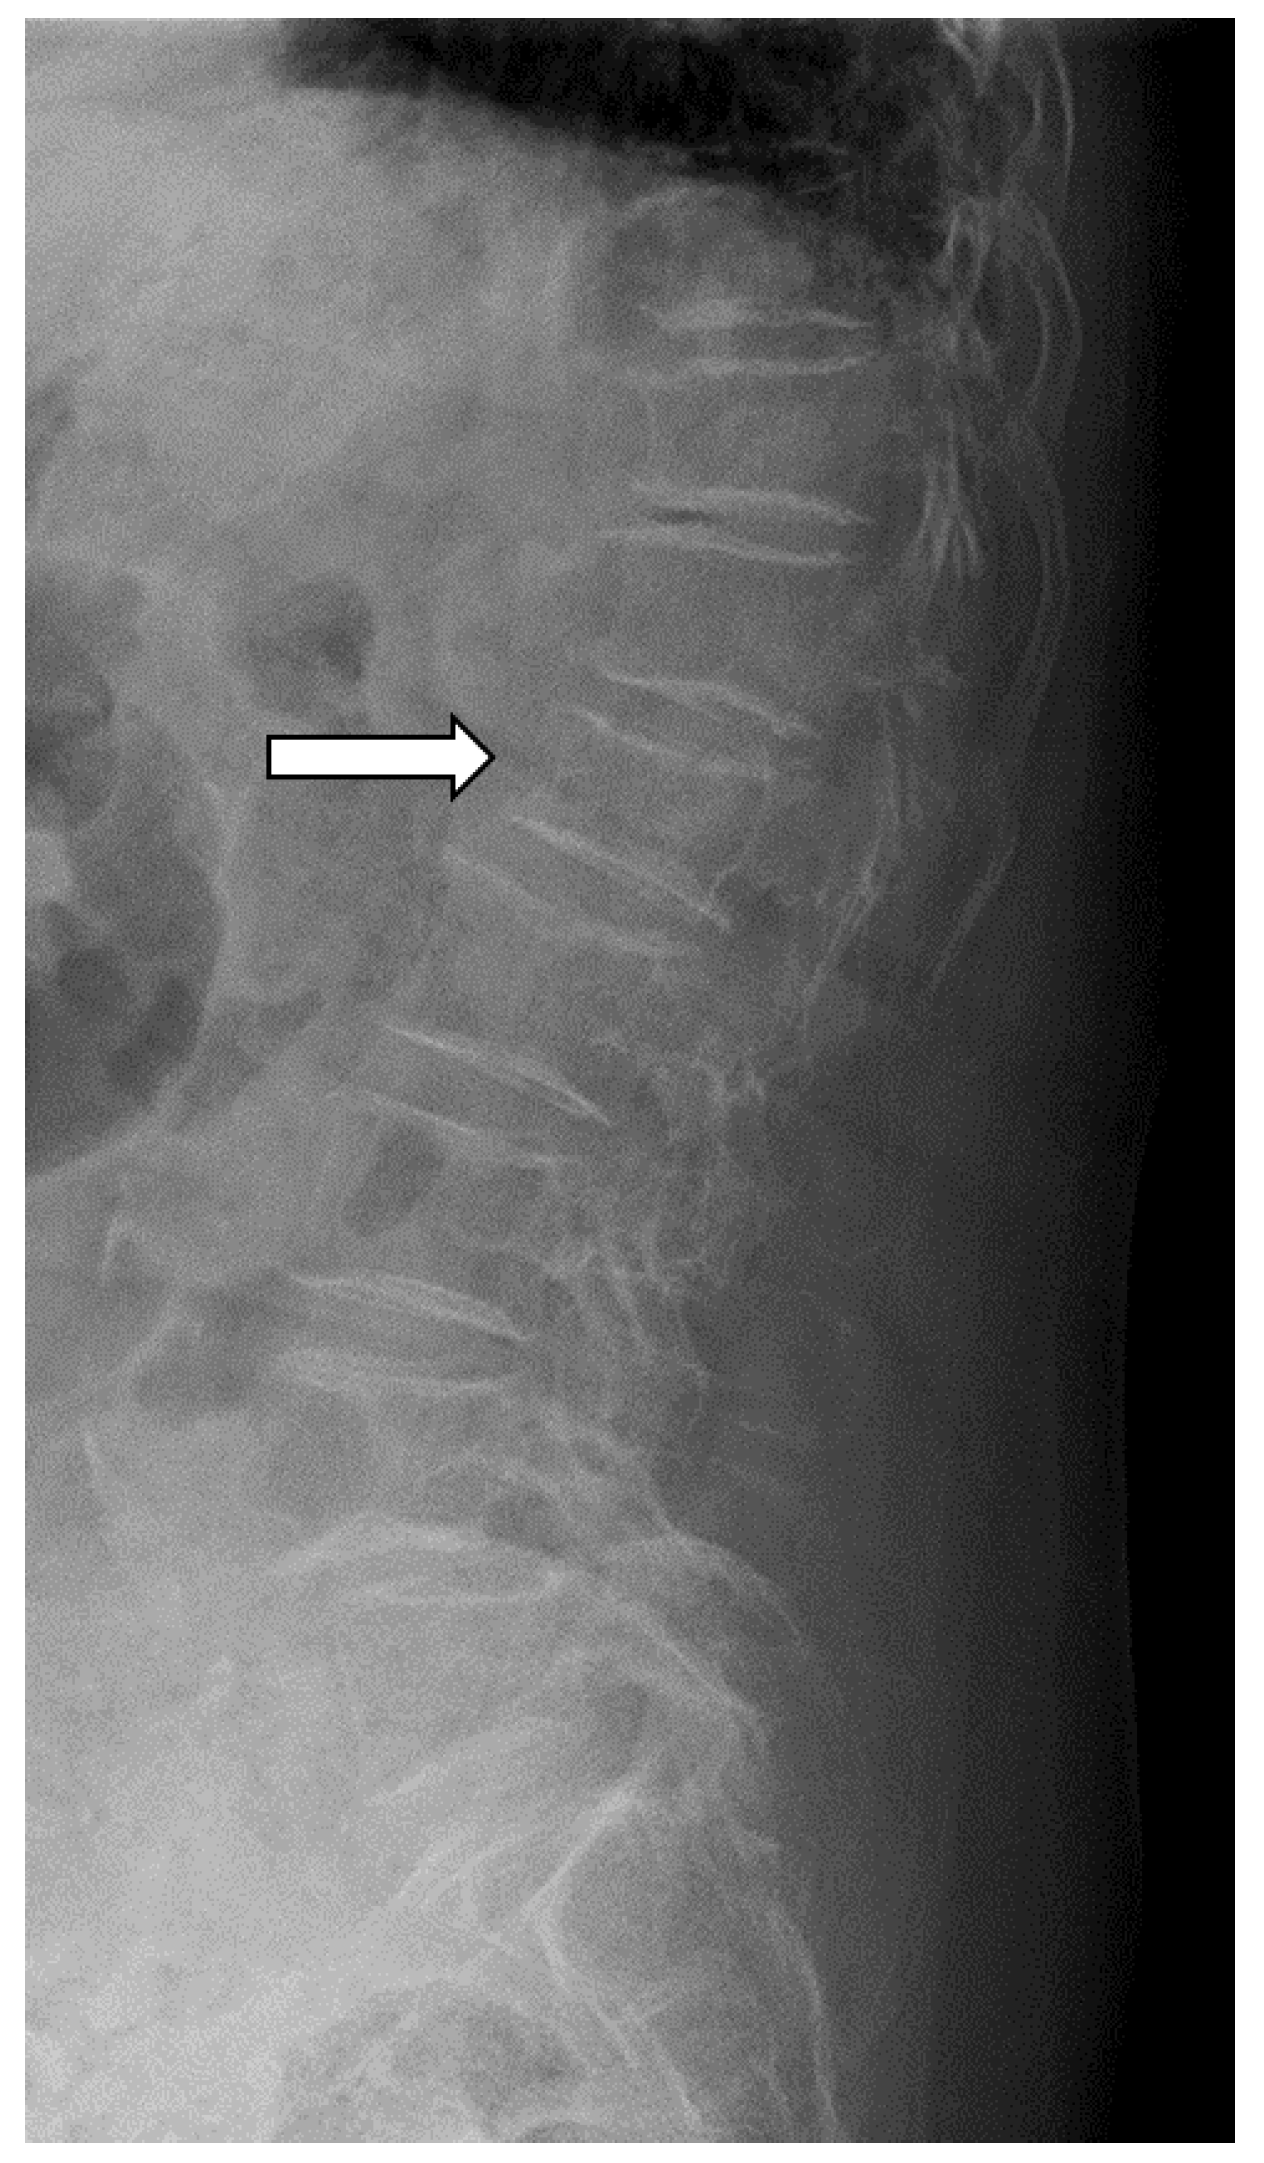

2.5. Radiological Assessment

- Genant, H.K.; Wu, C.Y.; van Kuijk, C.; Nevitt, M.C. Vertebral fracture assessment using a semiquantitative technique. J. Bone Miner. Res. 1993, 8, 1137–1148. [Google Scholar] [CrossRef] [PubMed]